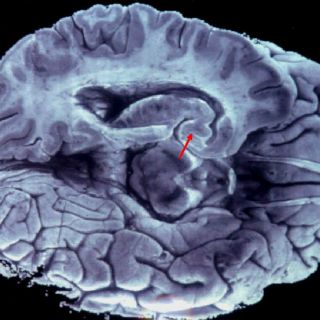

El equipo del ingeniero Tanaka logró este avance a través de mejorar la precisión de la tecnología de espectrometría de masas, lo que permite detectar en la sangre la acumulación de proteínas beta-amiloide, una de las probables causas del Alzheimer al afectar la transmisión entre las células nerviosas del cerebro.

Según las investigaciones, esta proteína se acumula en el cerebro durante un periodo de entre 10 y 15 años antes de que aparezcan los primeros síntomas de la enfermedad.